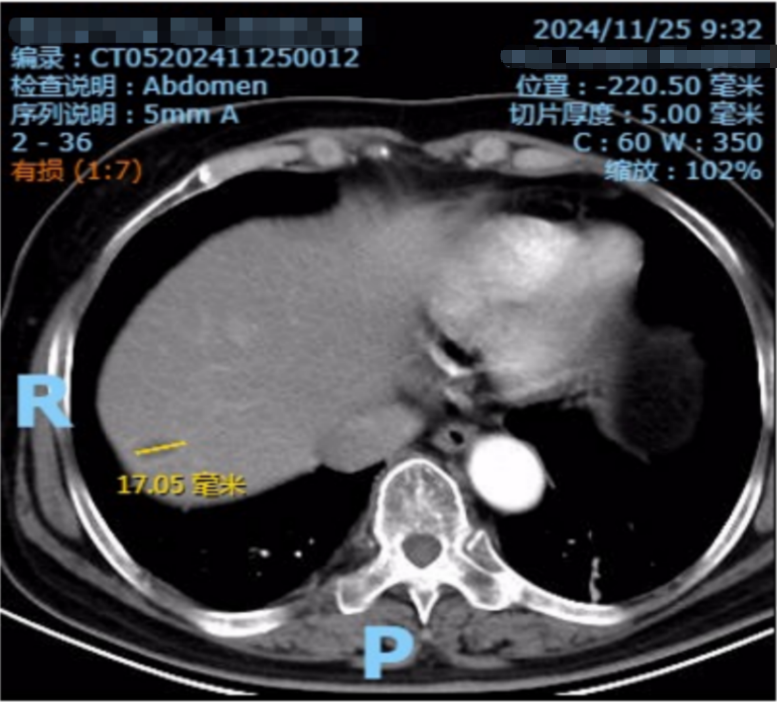

CT检查(2023年6月27日):胃壁改变,腹腔多发增大淋巴结,肝脏多发转移瘤(图1)。

图1. 基线CT检查(2023年6月27日)